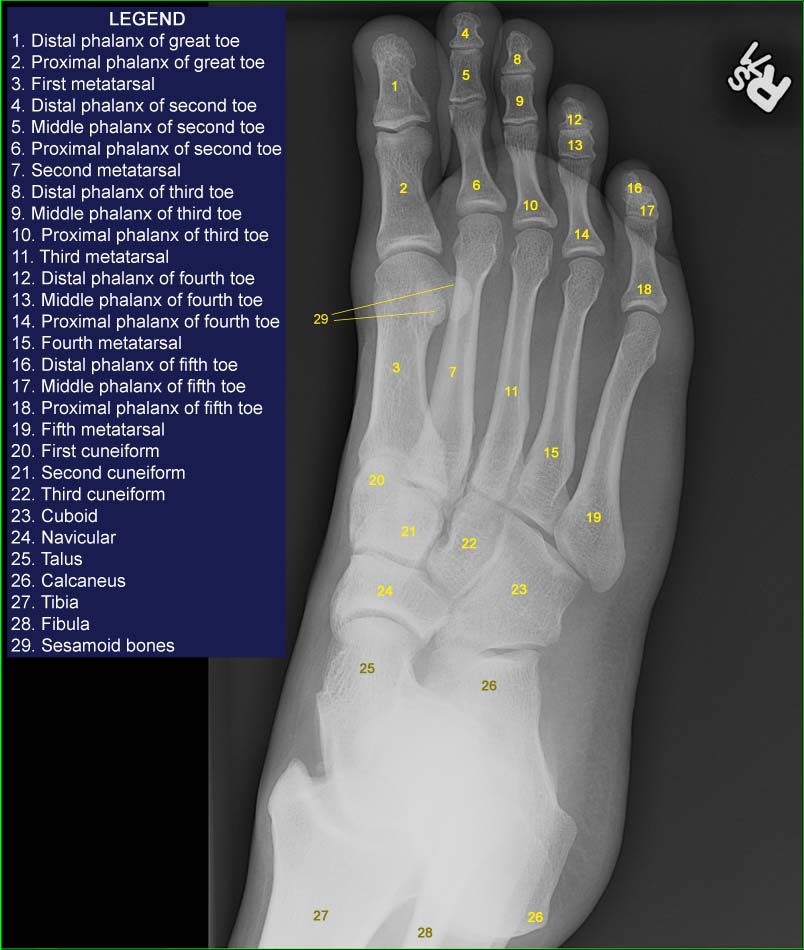

Right foot x-ray (oblique)

Legend